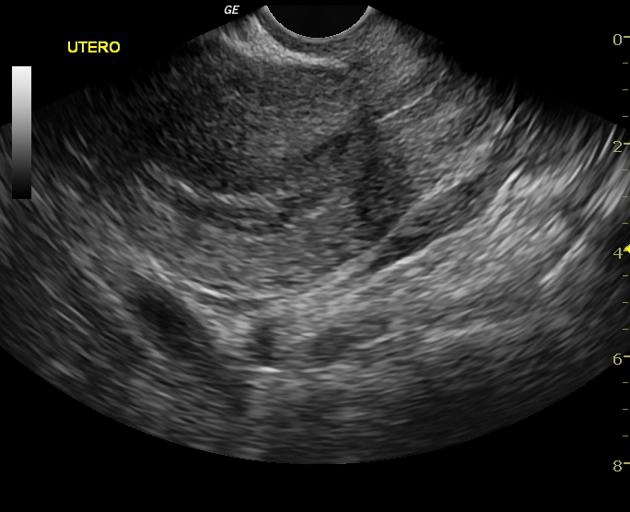

• VI. Thai ngoài tử cung

Thai bám sẹo mổ lấy thai (Cesarean section scar pregnancy)